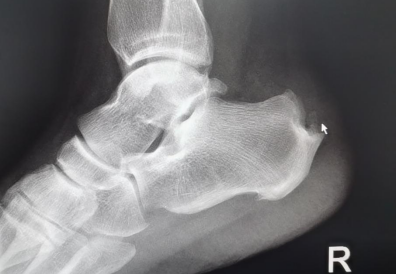

“经X光、磁共振等详细检查,提示患者双侧跟骨结节增生、跟腱有变性,双侧跟骨结节区域及跟腱止点表现:组织充血、水肿,结合病情及查体,考虑跟骨骨性突起畸形,经诊断,为Haglund综合症(止点性跟腱炎、跟骨后上突增生与跟腱滑囊炎的统称)。”李彬主任表示,该病症主要表现为跟腱止点部位疼痛不适,运动时疼痛加剧;或者清晨起床后出现疼痛,渐进性病程发展,后期疼痛加重,影响生活质量。